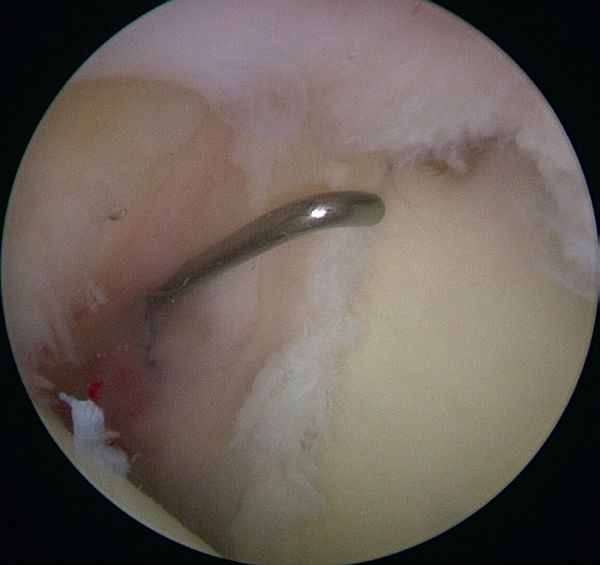

This progressive avulsion is taken-up by Burkhart et al. as the aptly termed ‘peel-back mechanism’ observed by reproducing the cocking phase under arthroscopic control, confirming the medial pivot of the posterosuperior labrum around the posterosuperior glenoid rim (Figure and Video).[6]

Peel-back mechanism

The beach-chair or supine position, with the arm free and not in traction, allows for dynamic tests under arthroscopic control; traction is then optional. The posterior approach (soft point) is lower than usual and slightly lateral, allowing a good view of the posterior labrum. The anterior approach in the rotator interval allows the insertion of a probe to confirm the need for repair. There are three signs required for positive arthroscopic diagnosis of a superior labral tear from anterior to posterior (SLAP) II lesion: a positive peel-back sign during dynamic cocking (the arm is abducted at 90 degrees and externally rotated at 90 degrees), a sublabral sulcus palpation > 5mm deep and a mobile labrobicipital complex. Two secondary instrumental incisions may be performed as required, using a small sleeve (spear guide < 4 mm), which is less traumatic for the rotator cuff and allows threading of anchors. The antero-lateral approach facilitates antero-superior anchoring of the glenoid rim (with an approach angle of 45 degrees) and the posterolateral Wilmington approach (1 cm from the posterolateral acromion angle and 1cm forward) allowing an angle of approach of 45 degrees to the posterosuperior angle of the glenoid).[55]